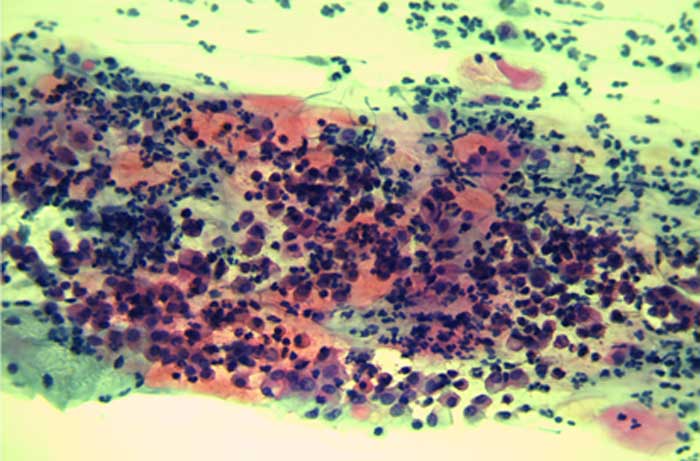

CIN-Stadien

Selten ergibt ein Abstrich einen auffälligen Befund, der eine Gewebeentnahme (Biopsie) nötig macht. Das Befundergebnis einer solchen kleinen Gewebeprobe wird nach Schweregrad in eine von drei CIN-Stadien eingeteilt. CIN bedeutet cervikale intraepitheliale Neoplasie und stellt eine Vorstufe von Gebärmutterhalskrebs dar.